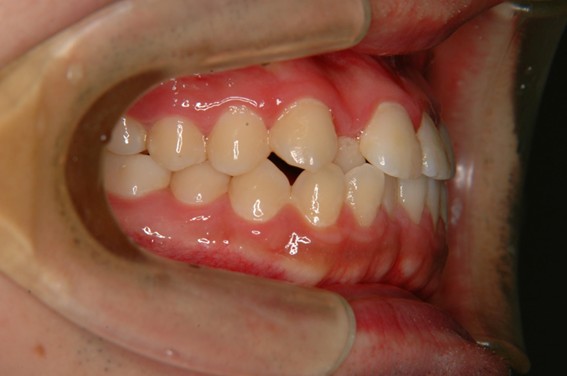

| 主訴 | 前歯が逆に噛んでいる。 |

| 治療内容 | 表側ワイヤー矯正、ジルコニア補綴を行いました。 |

| 治療費 | ワイヤー矯正660,000円(税込) ジルコニア176,000円(88,000円×2歯)(税込) |

| 治療期間 | 30ヶ月 |

| 治療回数 | 30回 |

| 想定されたリスク | 歯根吸収、歯髄壊死、歯髄充血、歯肉退縮のリスクがありました。 |

骨格性Ⅲ級・前歯部反対咬合の症例でした。反対咬合のまま治療していた前歯のサイズ不調和を、表側ワイヤー矯正とプロビジョナルクラウンで調整。正中を整え、犬歯・臼歯ともⅠ級、適切なオーバージェット(上下前歯の前後的な距離)・オーバーバイト(上下前歯の垂直的な重なり)に仕上げました。